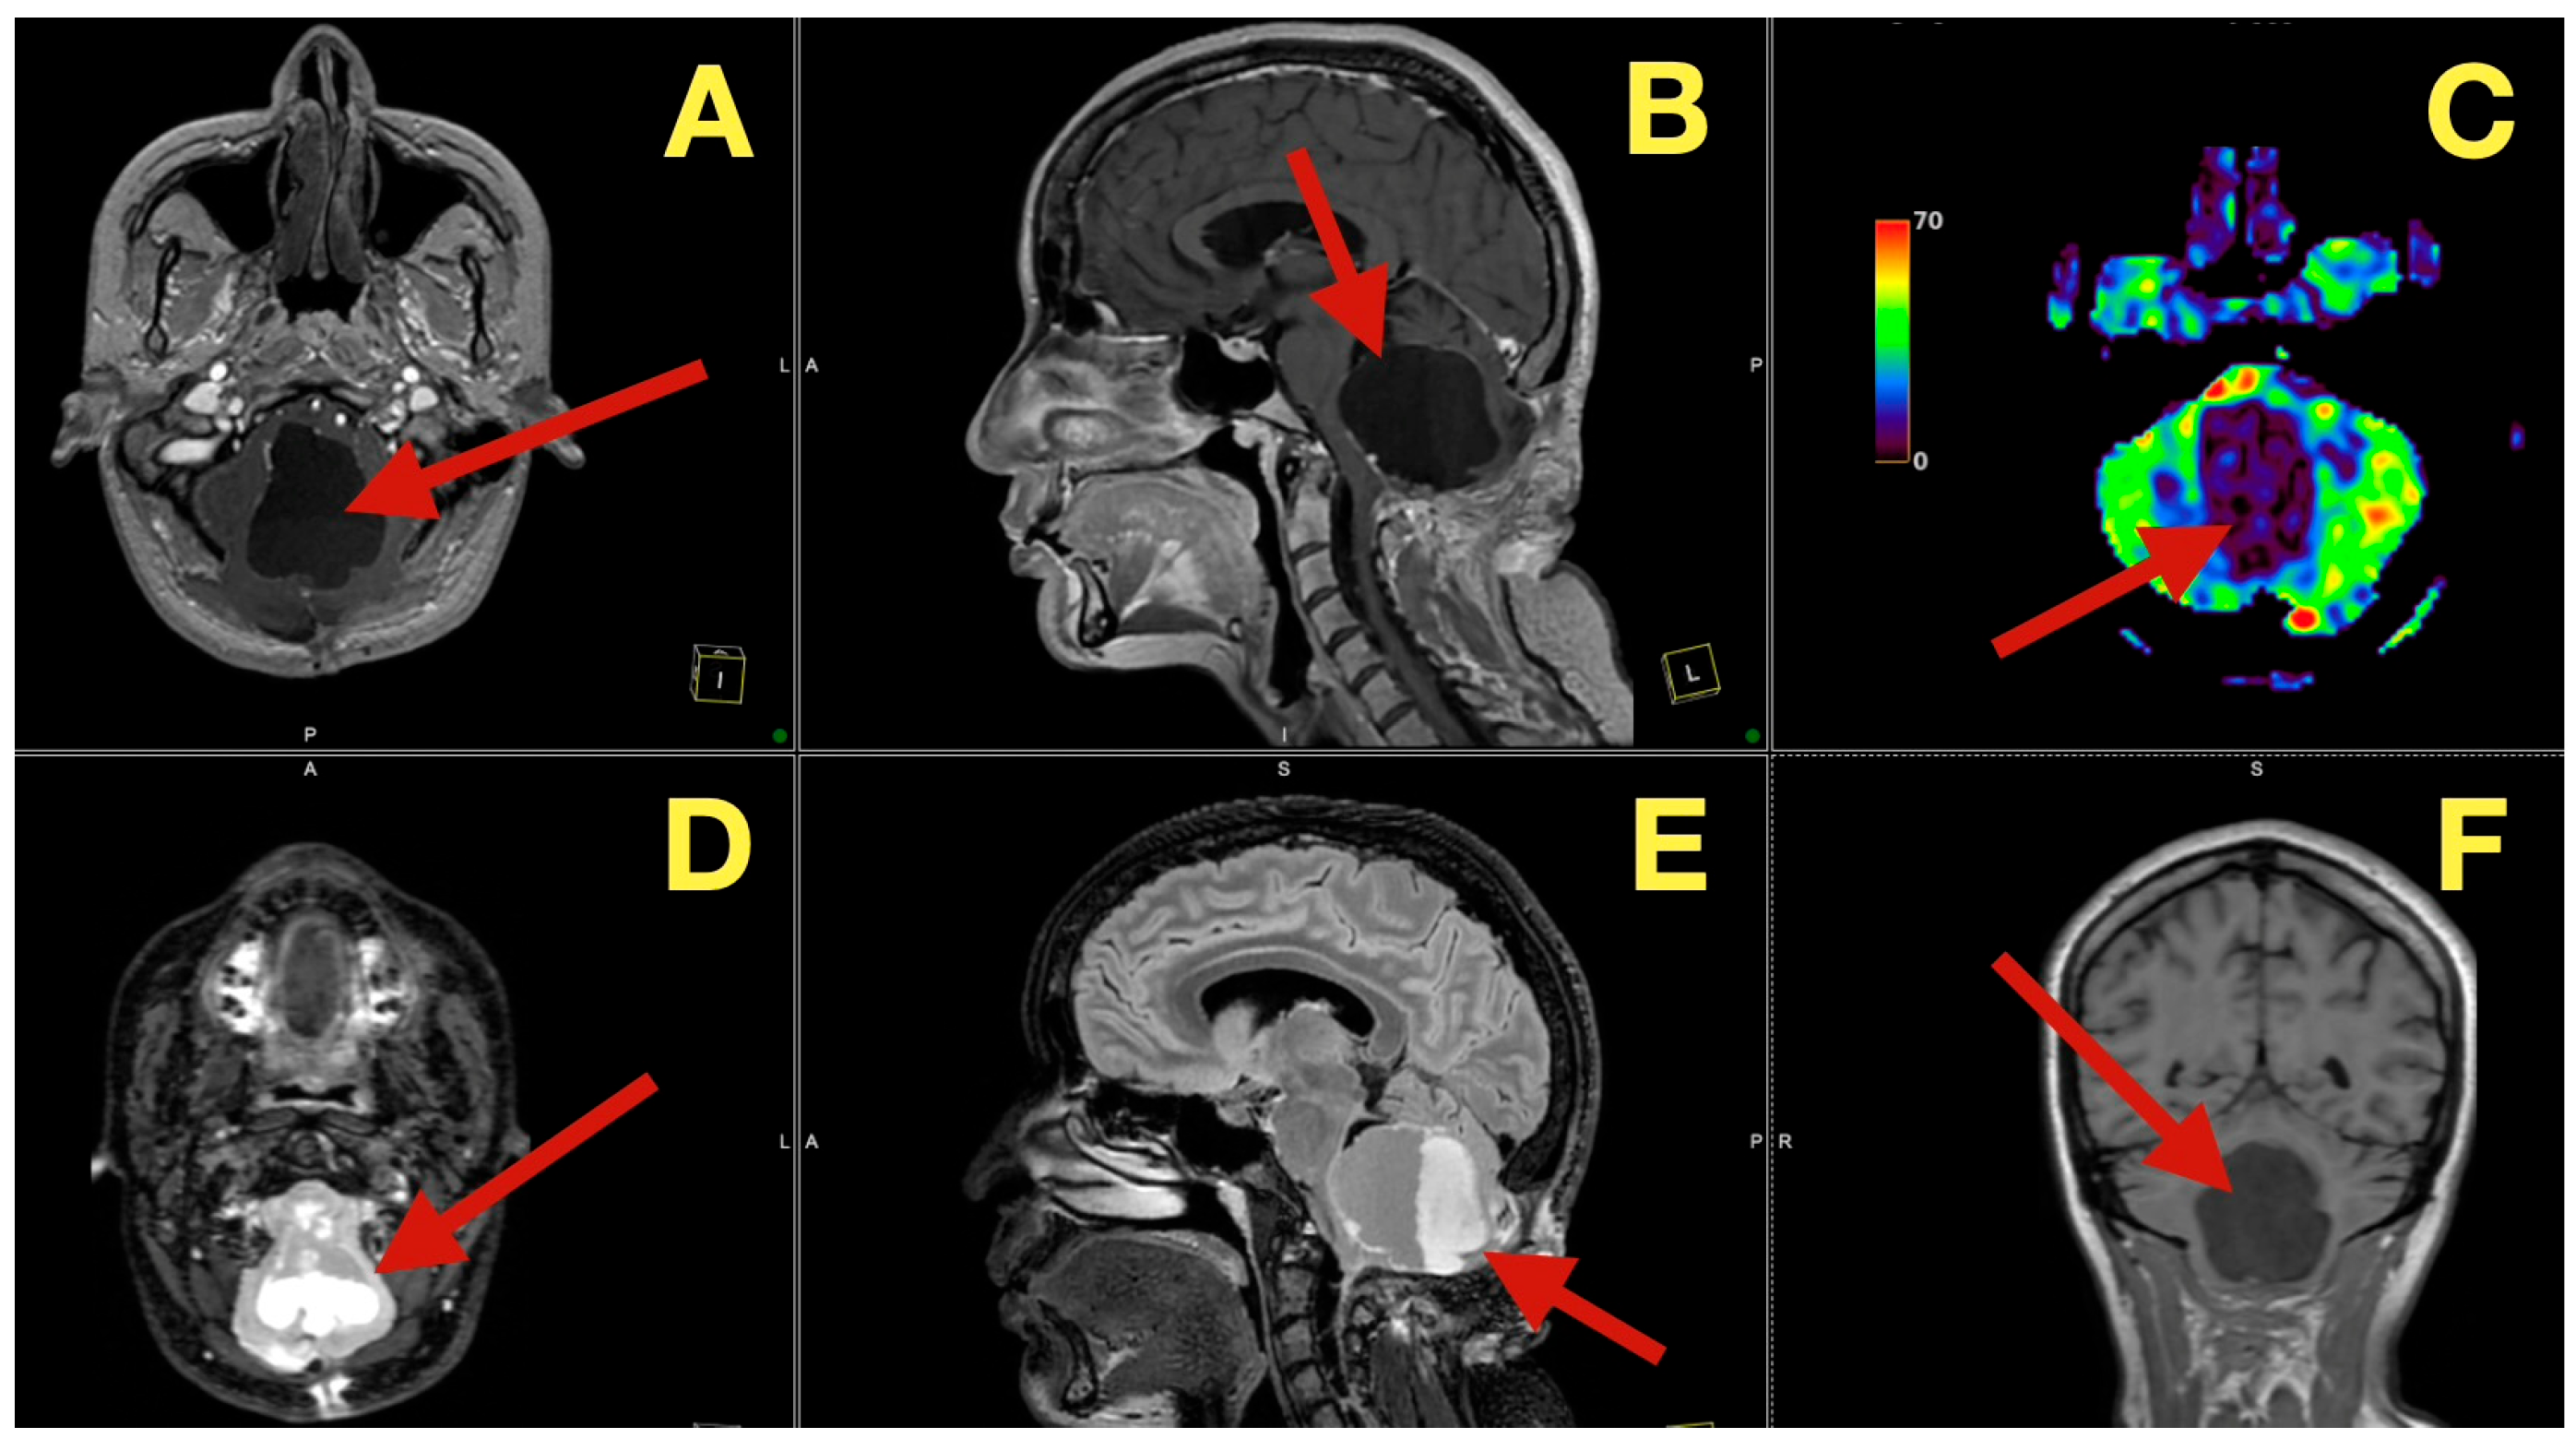

MRI scans five months after surgery (Figure 7), demonstrated that the post-operative cavity contained fluid with no enhancement and normal perfusion of the surrounding parenchyma, with no glial scar on FLAIR and no diffusion restriction on DWI, effectively ruling out remaining keratinous material.

Figure 7.

Five-month postoperative MRI. (A): Axial T1-weighted image demonstrating a CSF-filled postoperative cavity with smooth margins and no enhancing tissue (arrow). (B): Sagittal T1 image showing sustained patency of the fourth ventricle and normal vermian convexity (arrow). (C): Axial perfusion map revealing normal parenchymal hemodynamics in the cerebellum surrounding the resection site (arrow). (D): Axial diffusion-weighted image showing absence of restricted diffusion, excluding residual keratinaceous material (arrow). (E): Sagittal FLAIR sequence illustrating clean CSF spaces and absence of gliosis (arrow). (F): Coronal T1 image confirming midline symmetry and complete restitution of cerebellar and brainstem anatomy (arrow).